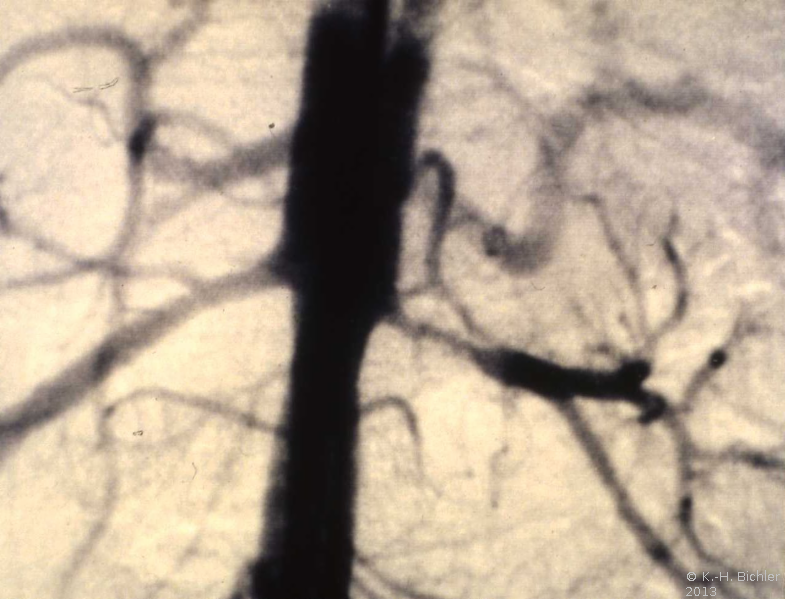

Die Röntgenübersicht der Niere und ableitenden Harnwege zeigten keinen Anhalt für Konkrement. Im Ausscheidungsurogramm eine "stumme Niere" links (Abbildung 19a). Bei der retrograden Sondierung links fand sich keine Abflussbehinderung (Stein oder Stenose) (Abbildung 19c). Im MCU kein Anhalt für Reflux (Abbildung 19b). Im Nierenfunktionsszintigramm MAG3 wurde eine seitengetrennte Funktionsverteilung von rechts zu links wie 93% zu 7% festgestellt. Zur Abklärung eventueller Gefäßalterationen erfolgte eine Renovasographie mit dem Nachweis einer langstreckigen Stenose der linken Arteria renalis (Abbildung 19d). Wegen des Verdachtes auf eine generalisierte Arteriitis wurden Angiographien weiterer Gefäßgebiete durchgeführt: Dabei fanden sich eine geringgradige Einengung der infrarenalen Aorta und der linken Arteria subclavia.

Diagnose: Generalisierte Arteriitis - Takayasu-Syndrom

Die Behandlung umfasste neben der perkutanen, transluminalen Dilatation der A. renalis die systemische Behandlung mit Cortison und β-Blocker. Unter dieser Behandlung kam es zur Verbesserung der linksseitigen Nierenfunktion auf 30%. Das AUR zeigte eine zeitgerechte Kontrastmittelausscheidung (Abbildung 20). Im weiteren Verlauf ist evtl. eine neuerliche Dilatation erforderlich bzw. eine operative Versorgung der Nierenarterienstenose.